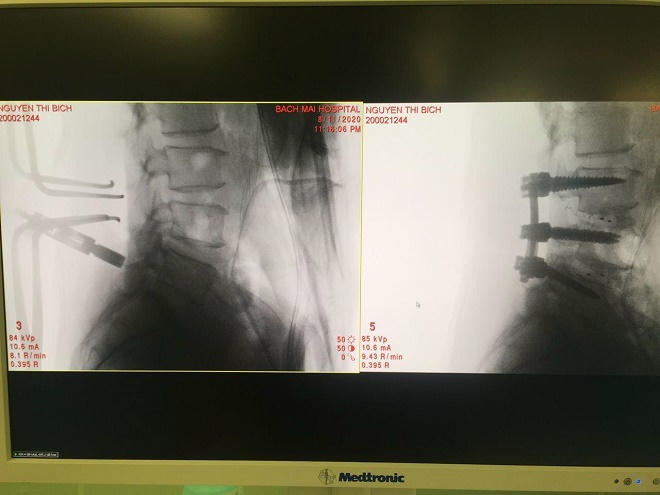

Trong quá trình phẫu thuật, đòi hỏi bác sĩ vừa phải đảm bảo sự an toàn cho người bệnh, tránh làm tổn thương thêm cho tủy sống, rễ thần kinh, mạch máu, lại vừa phải xử lý được tổn thương (thoát vị đĩa đệm, trượt đốt sống, dị dạng, u đốt sống, chấn thương). Đồng thời tái tạo cấu trúc sinh lý của cột sống bằng việc sử dụng vật liệu thay thế như: nẹp vít, ốc, đĩa đệm nhân tạo, nẹp silicon.

Phương pháp sử dụng hệ thống O-arm kết hợp định vị Navigation giúp cung cấp hình ảnh chính xác trong phẫu thuật cột sống. Đây là một giải pháp tiết kiệm thời gian trong phẫu thuật cung cấp hình ảnh độ phân giải cao 3D cho phẫu thuật viên và tự động đồng bộ hình ảnh trên hệ thống định vị Navigation. Đặc biệt Hệ thống O-arm và Navigation với không gian 3 chiều cho phép định vị chính xác vị trí cần phẫu thuật, giảm thiểu tai biến.

“Chỉ sai lệch 1-2mm trong quá trình phẫu thuật cột sống có thể khiến cho bệnh nhận bị liệt, tàn phế suất đời, thậm chí tử vong…”- BS CKII Võ Đức Chiến nhấn mạnh. Do đó, việc ứng dựng hệ thống O-arm giúp cho bác sĩ tiến hành được các ca phẫu thuật bệnh lý cột sống cho người bệnh an toàn, hiệu quả hơn vì hệ thống này cung cấp hình ảnh không gian 3D với độ phân giải cao, toàn diện giúp cho bác sĩ phẫu thuật biết rõ chính xác vị trí cần can thiệp tại cột sống, nhằm tránh ảnh hưởng các tổ chức xung quanh.

TS. BS Phạm Anh Tuấn, Trưởng khoa Ngoại thần kinh Bệnh viện Nguyễn Tri Phương cho biết: “Kĩ thuật phẫu thuật cột sống dựa trên hình ảnh chụp O-arm và hệ thống định vị Navigation giúp ca phẫu thuật cột sống có độ chính xác cao, tránh được các rủi ro và biến chứng cho bệnh nhân sau phẫu thuật”.

Việc sử dụng O-arm cùng với hệ thống định vị phẫu thuật, độ chính xác về vị trí bắt vít cột sống lên đến 93% - 100% so với tỷ lệ từ 72% - 92% của phương pháp thông thường. Hơn nữa, hệ thống này còn rút ngắn thời gian phục hồi của bệnh nhân, với bệnh nhân bị cong vẹo cột sống được thực hiện phẫu thuật bằng O-arm sau 3 ngày đã có thể đi lại được bình thường.